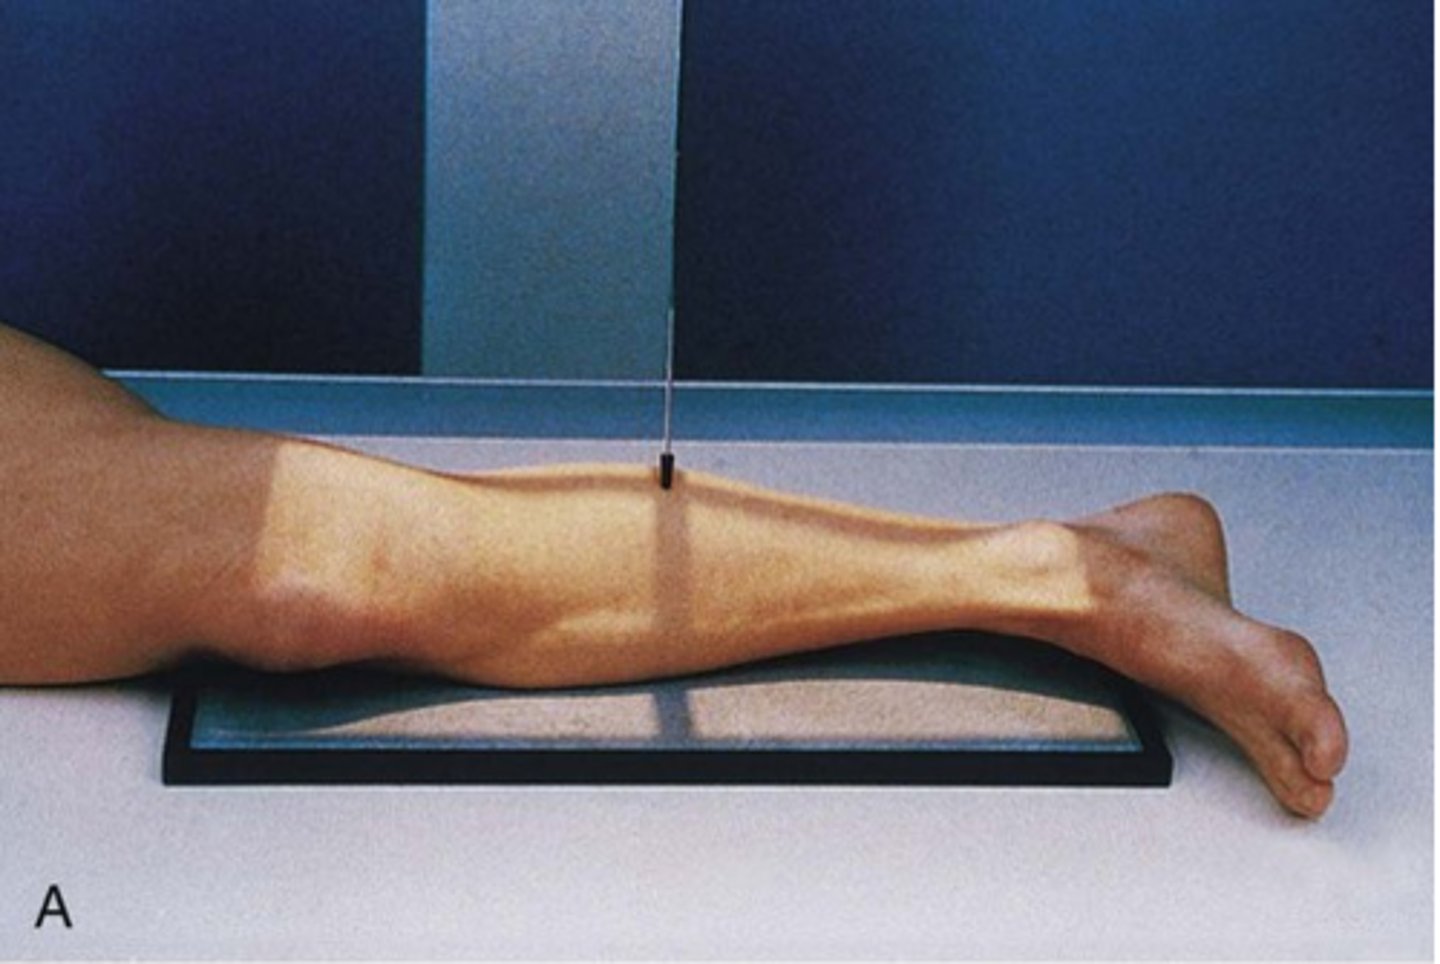

Describe, in detail, the positioning of the PATIENT for an AP TIBIA & FIBULA projection.

1. Patient sits upright or lies supine on the x-ray couch with the affected leg extended.

2. The posterior aspect of the affected leg should be in contact with the IR.

3. The limb is rotated medially until the medial and lateral malleoli are equidistant from the image detector. The condyles of the knees should also be equidistant to the image detector.

4. The ankle is also dorsi-flexed (toes pointing upwards) to open up the mortise joint.

How should we position the X-RAY TUBE for an AP projection of the TIBIA & FIBULA?

SID

Central ray

Centring point

SID: 100 - 115cm (115cm may be needed for patients with long legs)

Central ray: perpendicular to the IR

Centring point: in the midline of the limb, midway between the knee and ankle joint

How should we COLLIMATE when doing an AP projection of the TIBIA & FIBULA?

- to include the entire length of the tibia and fibula bones and lateral soft tissue borders. The knee and ankle joint must also be included.